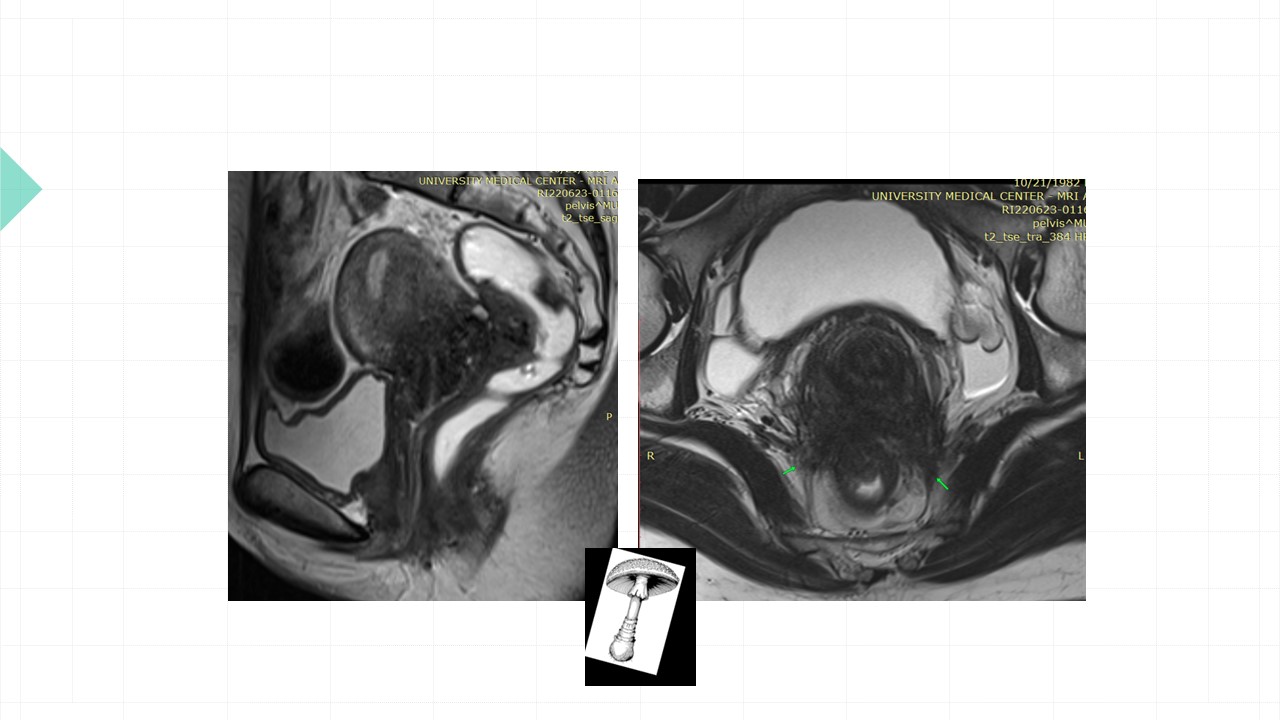

Vai trò cộng hưởng từ trong đánh giá lạc nội mạc tử cung

Từ khóa: Vai trò cộng hưởng từ trong đánh giá lạc nội mạc tử cung